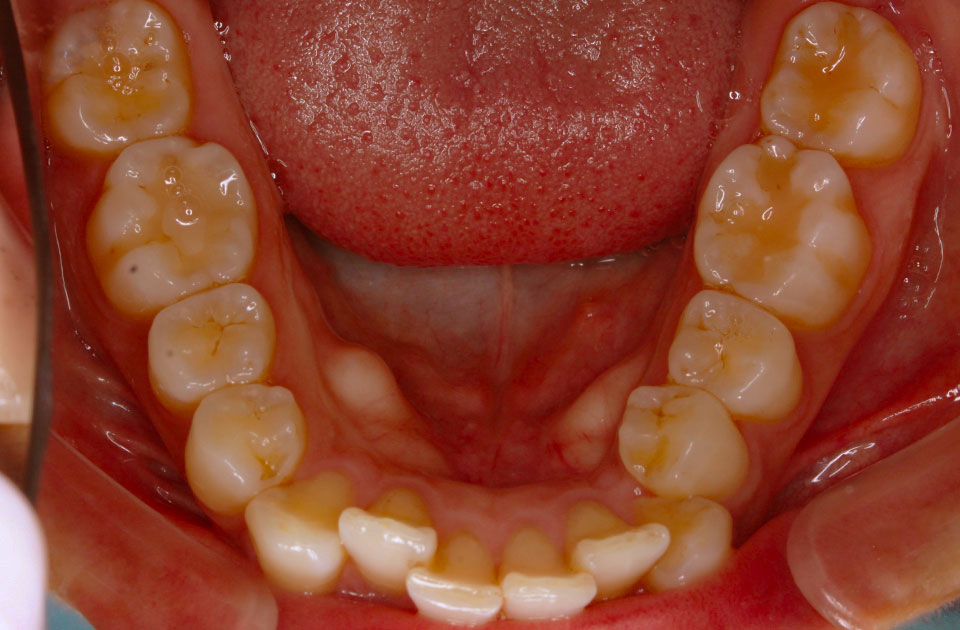

矯正前 下顎

矯正後 下顎